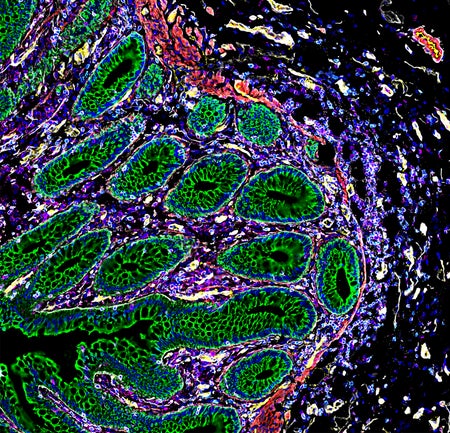

Cells Organize Themselves into ‘Neighborhoods’ That Could Shape Treatment

“Cell atlases” offer an unprecedented look at how kidney cells become diseased and how fetal cells invade and remodel the placenta’s blood vessels